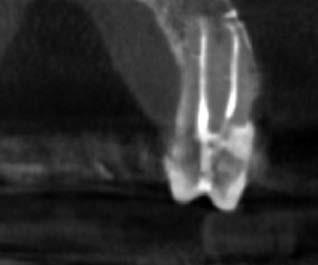

1. a-n. ábrák: Preoperatív CBCT-felvétel a bal alsó 6-os (3.6) fogról. Az axialis (a), coronalis (b) és sagittalis (c) nézeteken a mezialis és distalis gyökerek apicalis harmada körül sugáráteresztő zóna és ép buccalis corticalis csont látható. Egy olyan sablont terveztünk, amely jelezte a csontablak határait az apicalis terület pontos elérése érdekében (d). A mikrosebészeti bevatkozás során a sablont a helyére illesztettük (e), a csontablak határait megjelöltük (f) egy Piezotome CUBE LED kézi-darabba fogott fűrésszel, majd kivágtuk és eltávolítottuk (g és h) az apicalis területhez történő hozzáférés, illetve a mezialis és distalis gyökerek rezekciójának, retrográd preparációjának és retrográd gyökértömésének elvégzése érdekében (i). Végezetül a csontablakot visszaillesztettük és kollagén szivaccsal stabilizáltuk (j). A műtét után közvetlenül készített röntgenfelvétel a 3.6-os fogról (k). A kétéves kontroll során készített CBCT-felvétel: axialis (l), coronalis (m) és sagittalis (n) nézetek.

Egy 63 éves páciens korábban már kezelt bal alsó első nagyőrlőfogából (3.6) eredő mérsékelt fájdalom miatt kereste fel rendelőnket. A kórtörténetében panasza szempontjából releváns információ nem szerepelt. Az elkészült CBCT-felvételen a korábbi kezelések során észre nem vett, jelenleg feltáratlan meziobuccalis csatornát, valamint a mezialis és distalis gyökerek körül kialakult periapicalis elváltozást, és ezt a léziót borító intakt buccalis corticalis csontlemezt láttunk.

Klinikai vizsgálat során vertikális kopogtatási érzékenységet jelzett. A fog körül mérhető szondázási mélység és a fogmobilitás fiziológiás volt. A CBCT-felvételen nem észleltünk a csontos regeneráció megindulására utaló jeleket (1. a–c. ábrák). A korábban gyökérkezelt, gyökértömött és revideált 3.6-os fog esetében az alábbi diagnózis került felállításra: periodontitis periapicalis symptomatica. A panaszokat okozó fog további ellátása során navigált endodonciai mikrosebészetet kívántunk alkalmazni. Az alsó állcsontról intraorális szkent (TRIOS, 3Shape) készítettünk, és a felszíni topográfiát tartalmazó STL fájlt, valamint a CBCT-felvétel készítése során nyert DICOM fájlokat a Blue Sky Bio szoftver segítségével egyesítettük. A sebészi sablon megtervezésére az így kapott háromdimenziós képet használtuk. A sablon kialakítása során arra törekedtünk, hogy a sablon egyértelműen meghatározza a gyökércsúcsi terület eléréséhez szükséges csontablak határait (1. d. ábra)